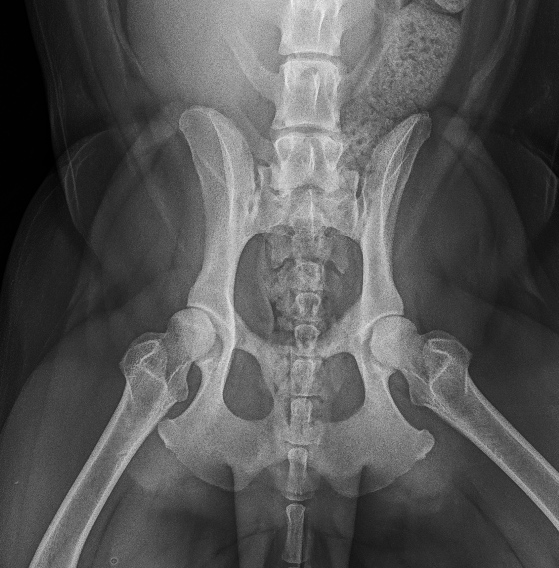

The Whyalla Veterinary Clinic has a new Shimadzu MUX10 Xray machine for high quality radiographs and a new Agfa XD14 Csi Tethered panel to produce outstanding direct digital Xrays from the images from the Shimadzu MUX10 Xray machine.

The XD14 CsI Tethered Panel is an integral part of an Agfa HealthCare’s Instant DR solution, which includes the NX image acquisition software with MUSICA3 processing and detector. These cassette-less and filmless solutions provide a range of workflow benefits that improve quality, productivity and speed up exam time.